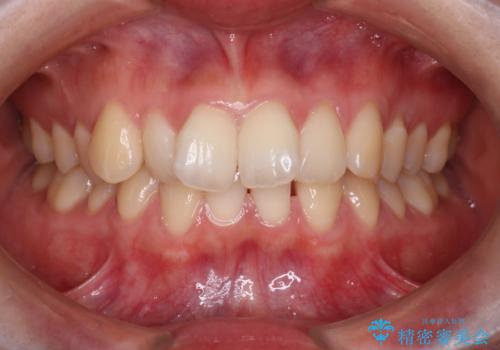

[マウスピース矯正] 海外留学中でも可能な矯正治療

担当医 大元洋佑

![[マウスピース矯正] 海外留学中でも可能な矯正治療の症例 治療前](https://seimitsushinbi.jp/wp/wp-content/uploads/2025/01/C4-1-500x350.jpg?v=1737343006)

![[マウスピース矯正] 海外留学中でも可能な矯正治療の症例 治療後](https://seimitsushinbi.jp/wp/wp-content/uploads/2025/01/IMG_0074-500x350.jpg?v=1737343049)